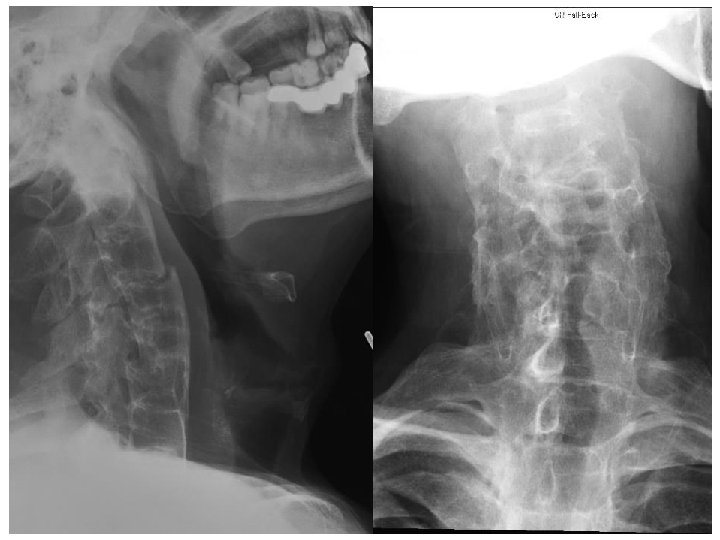

Case 3 • M/66 longstanding back pain • Taxi driver, sprained neck when hit by private car from behind in front of a traffic light in street • Exact speed unknown, seat belt on • He complained of severe neck pain • Physical exam showed severe mid-cervical tenderness • 4 limbs power full

Describe the injury (3 marks) • C 1 to inferior plate of C 7 visible • Anterior translocation of C 4 and C 5 relative to both upper and lower vertebrae • Disruption of the calcified anterior longitudinal ligament over C 3/4 • Possible transverse fracture of inferior facet joint of C 3 • Overall, there is acute transdiscal fracture over C 3/4 IVD with anterior displacement of the vertebral column

Notes • It is difficult to determine whether the facet joint disruption is unilateral or bilateral from these X-ray films • C 5 is also displaced anteriorly over C 6 • Likely old injury as C 5/6 fusion is seen • The opacified ALL is not disrupted

Describe other XR abnormalities (3 marks) • In addition to the injury, underlying ankylosing spondylitis is seen, as evidenced by ◦ Sclerosis of superior and inferior margins of vertebral bodies (Romanus lesion) ◦ Extensive syndesmophytes formation, bridged, resulting in a bamboo spine appearance ◦ Opacification of the anterior longitudinal ligament

What further investigation will you perform? (2 marks) • Plain CT scan of C-spine • MRI scan of spinal cord

Describe the MRI findings (3 marks) • There is anterior translocation of C 4/5 • Narrowing of spinal canal • Impingement on spinal cord • No acute hematoma seen • No acute cord edema seen on T 2 sequence

Notes • The patient probably has no acute cord transection ◦ However there can still be cord damages due to spinal shock, cord infarction ◦ The fracture is unstable and the patient is at high risk of cord injury • The normal diameter of the cervical spinal canal is around 17 mm. ◦ The average diameter of the spinal cord in the C-spine is 10 mm ◦ 10 mm to 13 mm is likely to cause symptoms ◦ <10 mm is clearly stenosis ◦ No clear consensus on radiological criteria for diagnosis of spinal stenosis